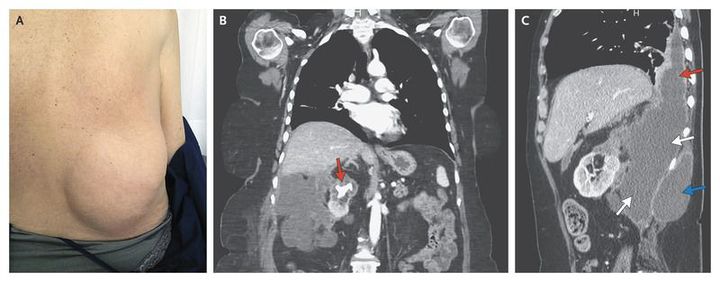

A 65-year-old woman presented to the hospital with a 4-month history of intermittent low-grade fever, asthenia, anorexia, and weight loss. Her medical history was limited to atrophic gastritis treated with intramuscular vitamin B12. Physical examination revealed a large, soft mass protruding from her right flank (Panel A, view from posterior). Blood tests showed a leukocyte count of 17,900 per cubic millimeter (90% neutrophils), a hemoglobin level of 9.8 g per deciliter, a C-reactive protein level of 274 mg per liter, and an erythrocyte sedimentation rate of 104 mm per hour. Blood cultures were negative. Computed tomography of the abdomen with the use of contrast material revealed a large, obstructing calculus in the upper-pole calyx of the right kidney, causing focal atrophy and cortical thinning of the upper pole (Panel B, arrow); there was also a large retroperitoneal abscess (Panel C, white arrows) extending into the chest (Panel C, red arrow) and subcutaneous tissues of the right flank (Panel C, blue arrow). A urine culture was positive for Proteus mirabilis, as was a culture of fluid drained percutaneously from the abscess. A right nephrectomy was performed. Histologic examination revealed an abscess with chronic inflammation and no xanthogranulomatous changes. The patient was doing well 18 months after surgery.